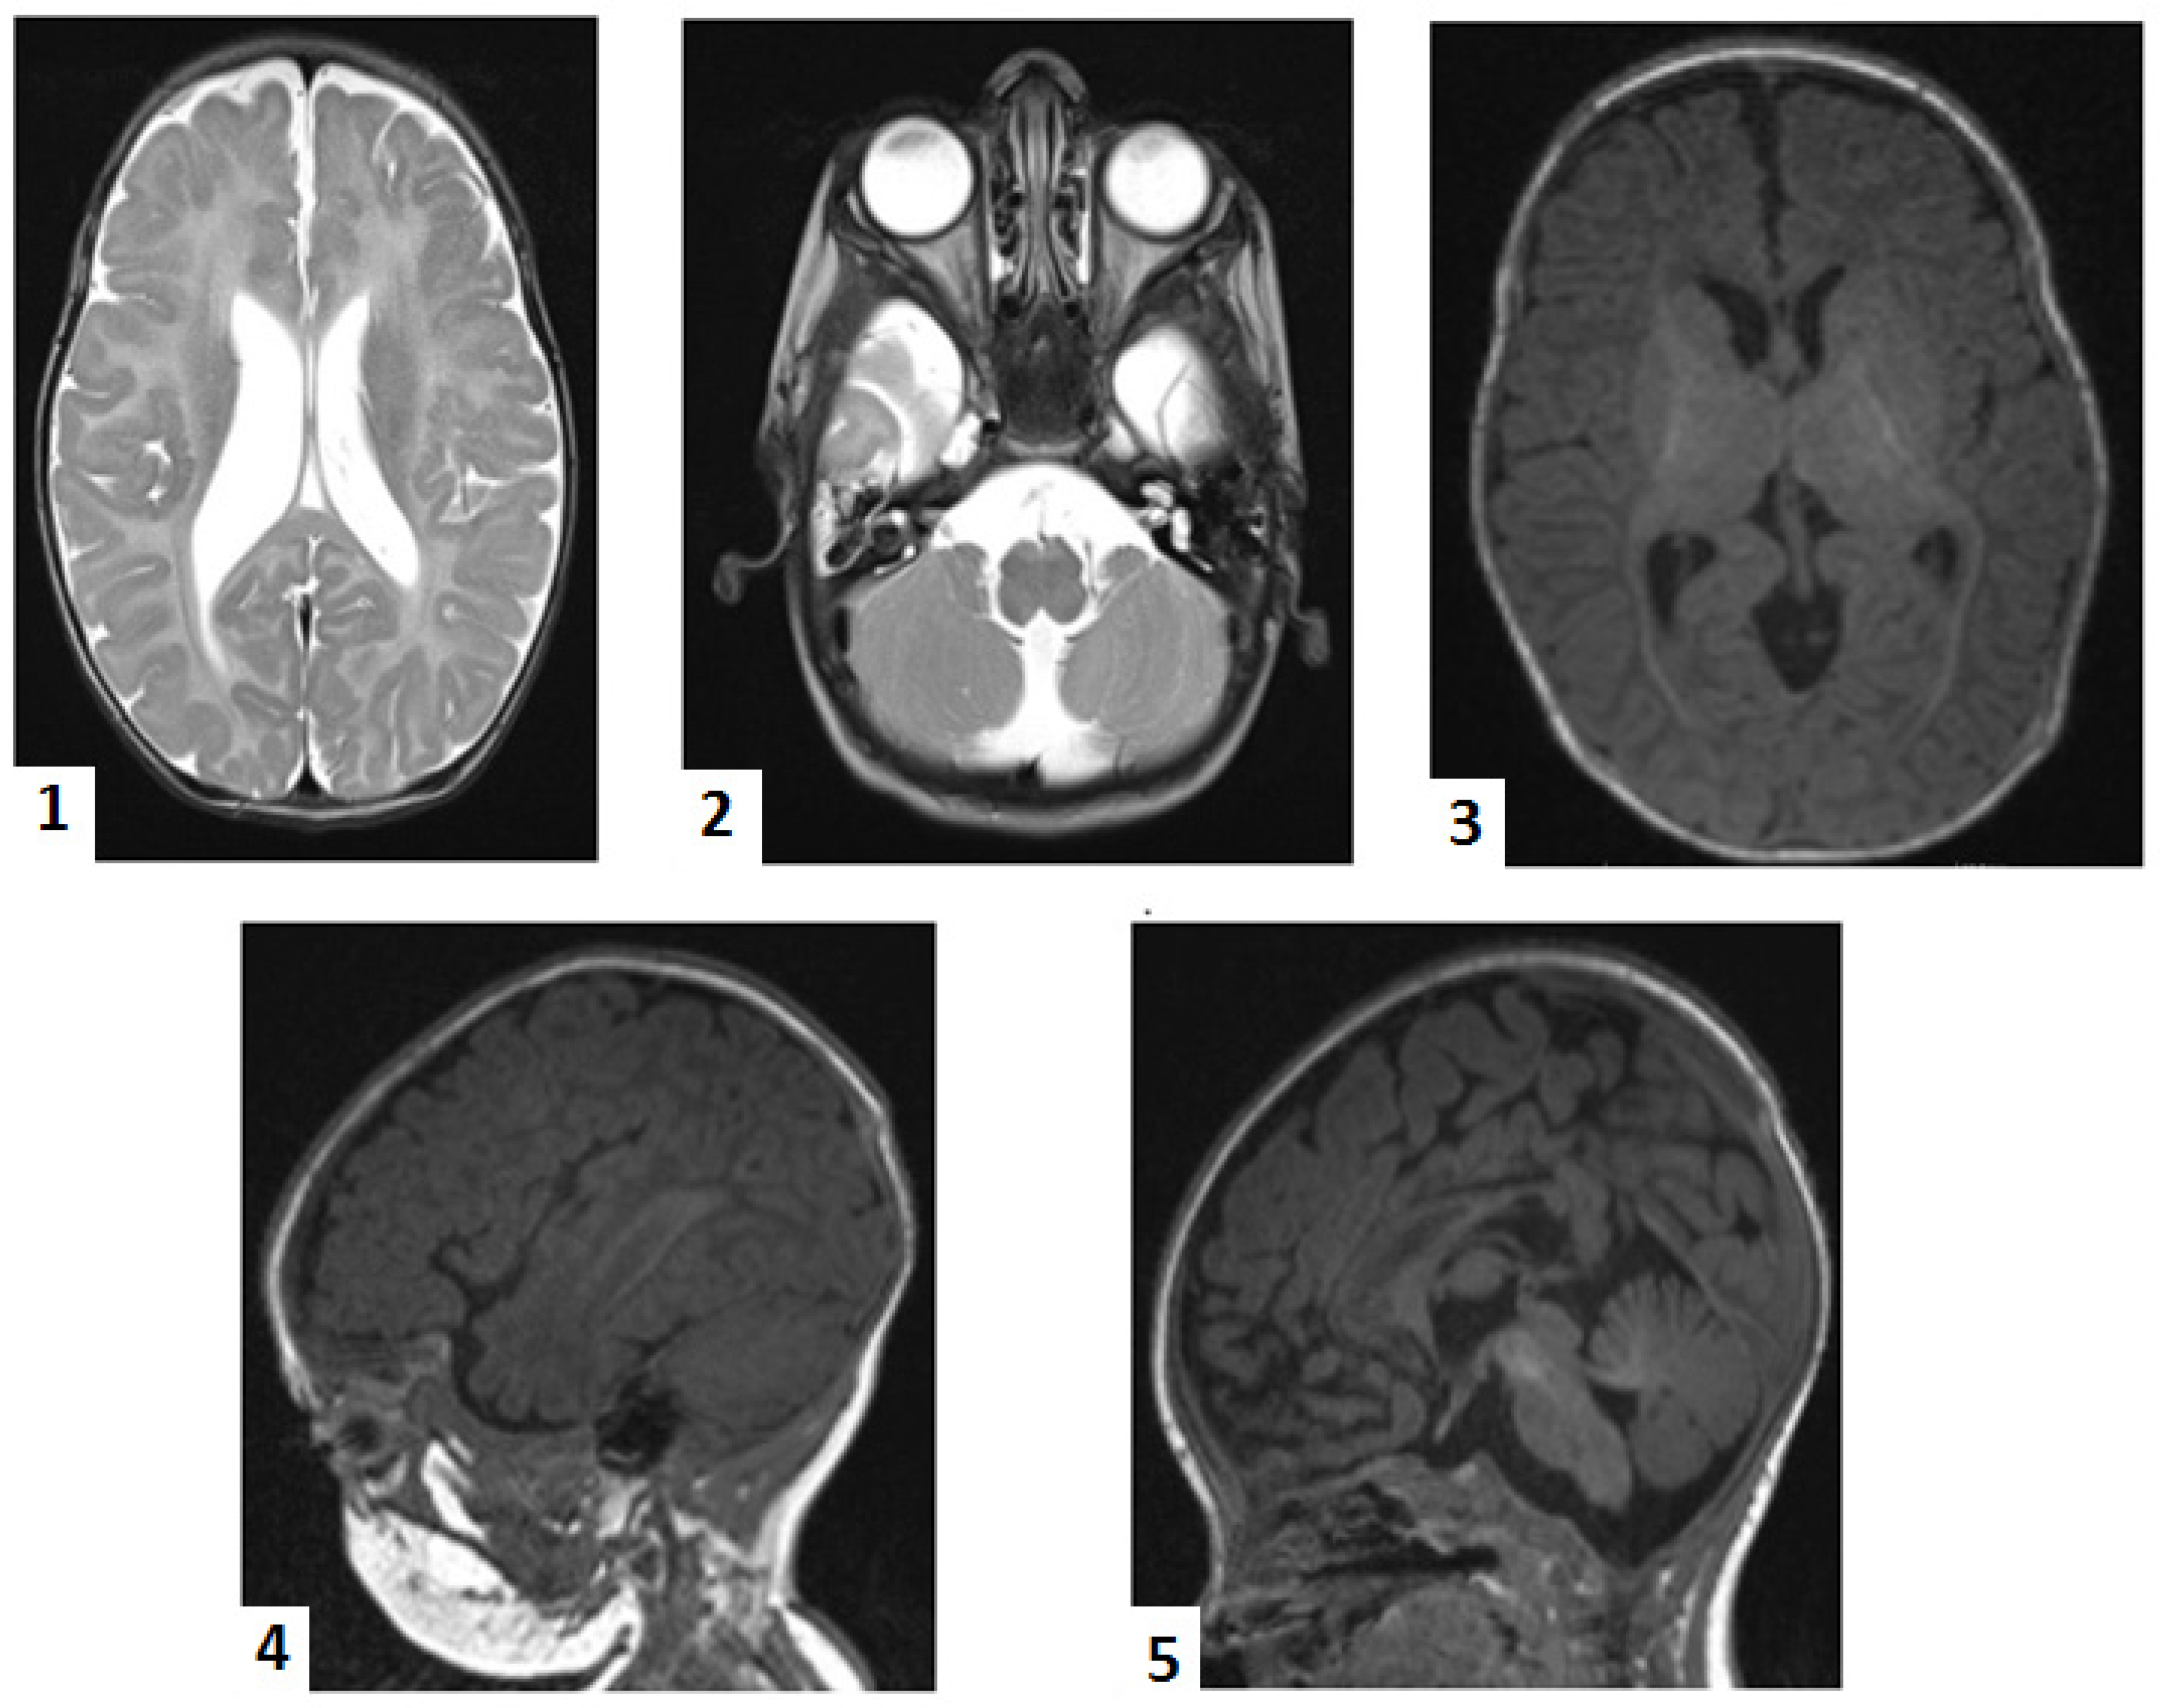

A typical and classic approach to D-BPD diagnosis involves several laborious steps [14,20] (Figure 5). The clinical suspicion is usually based on neonatal (even congenital) hypotonia, neonatal seizures, and facial dysmorphism [2,7,9,11,18]. Neuroimaging provides valuable information for the diagnosis, generally directed toward a neurodegenerative hereditary metabolic condition [4,18]. The next step involves measuring biochemical markers, followed by genetic testing, and finally, using skin fibroblast culture, direct measurement of the deficient enzyme and evaluation of C26:0 β-oxidation [2,5,9]. However, clinical aspects may not be suggestive; symptoms of the perinatal condition may overlap or may be similar to those of a rare disease, as early onset neonatal sepsis and perinatal hypoxia did in our patient. It is even more challenging to consider a genetic condition in the absence of physical markers that suggest a chromosomal abnormality.

Figure 5. Diagnostic approach pathways in D-bifunctional protein deficit (D-BPD) during neonatal period. Legend: 1—hypotonia is present at birth in 98% of cases; 2—seizures occur at birth in 93% of cases and are refractory to anticonvulsants; 3—suggestive facial dysmorphism includes high forehead, hypertelorism, epicanthus, upslanted palpebral fissure, long philtrum, depressed nasal bridge, high arched palate, large fontanelle, retrognatism, macrocephaly, and low-set ears (most aspects are similar to Zellweger syndrome); 4—in severe forms of D-BPD, infants do not acquire any developmental skills; in mild forms, with some residual protein activity, infants may reach very early developmental milestones but gradual developmental regression is noted within a few months, and hyperreflexia and hypertonia develop with D-BPD progression; 5—routine biochemical tests, blood gases analysis, neonatal imaging (X-rays, ultrasound brain, heart, and abdomen), amplitude and conventional integrate electroencephalography, auditory and visual tests, DNA analysis that may exclude perinatal hypoxic–ischemic encephalopathy, neonatal sepsis and meningitis, chronic infections (TORCH syndrome), congenital brain abnormalities, and congenital neurological or muscular diseases; 6—D-BPD cases were reported in association with abnormal prenatal development (fetal ascites, polyhydramnios), other metabolic or homeostasis abnormalities (such as increased transaminases), digestive tract abnormalities (bile duct proliferation, cholestasis, hepatomegaly, hepatic steatosis, feeding difficulties), endocrine problems (primary adrenal insufficiency), renal cysts, splenomegaly, ocular abnormalities (nistagmus, strabismus, visual loss), osseous and muscular abnormalities (frontal bossing, dolichocephaly, clubfoot, hammertoe, split hand, clacific stippling, delayed skeletal maturation, osteopenia, decrease muscle mass), hearing impairments, central nervous system abnormalities (cerebral dysmyelination or hypoplasia, gliosis, cortical dysplasia, cerebellar atrophy, callosal hypoplasia or atrophy, ventriculomegaly), and failure to thrive; 7—consanguineous parents or siblings with neurodevelopmental delay (alive or dead) are suggestive of rare hereditary conditions; *—biochemical markers may be normal during neonatal period; 8—VLCFA—very-long-chain fatty acid levels are increased; 9—phytanic acid and pristanic acid (the final product of phytanic acid α-oxidation) are increased secondary to impaired peroxisomal β-oxidation due to D-BPD; 10—dihydroxycholestanoic acid (DHCA); 11—trihydroxycholestanoic acid (THCA); DHCA and THCA plasmatic levels are increased due to D-BPD; 12—normal plasmalogen levels in red blood cells excludes generalized peroxisomal disorders; 13—genetic testing may help exclude epileptic syndromes with neonatal/infantile onset; 14—cultures’ skin fibroblasts help in diagnosis in infants with normal biochemical markers during neonatal period and differential diagnosis from Zellweger syndrome, and allow for quantification of the enzyme activity, which is of further help in predicting D-BPD course; 15—magnetic resonance imaging may show congenital brain defects (see above; Legend 6), abnormal/delayed myelination, white substance demyelination, neuronal migration disorders, focal heterotopia, and germinolytic cysts; MRI may show normal aspects during the neonatal period, followed, in time, by a suggestive model of cerebral and cerebellar leukoencephalopathy; 16—WES—whole-exome sequencing; 17—WGS—whole-genome sequencing; 18—HSD17B4 gene—17β-hydroxystroid dehydrogenase type 4 sequencing identifies the defect and its location and helps in predicting the patient’s outcome [2,3,4,5,6,7,8,9,10,12,15,16,18,19,20,28,34].